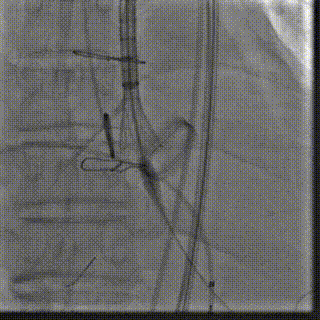

在右股动脉穿刺建立通路后,将右冠送入冠脉保护,后顺利送入大鞘,经食道超声及血管造影确认路径稳定,将ProStyle A ® AV32号瓣膜精准释放于目标位置(瓣下2mm),超声显示无瓣周漏,平均跨瓣压差4mmHg,心功能明显改善,患者生命体征平稳。

缓慢释放瓣膜

最终造影,位置形态良好,冠脉充盈良好

术后超声: 显示瓣膜呈现较好的圆形,最大流速133cm/s,平均跨瓣压差显著降低至4mmHg,瓣周无反流。